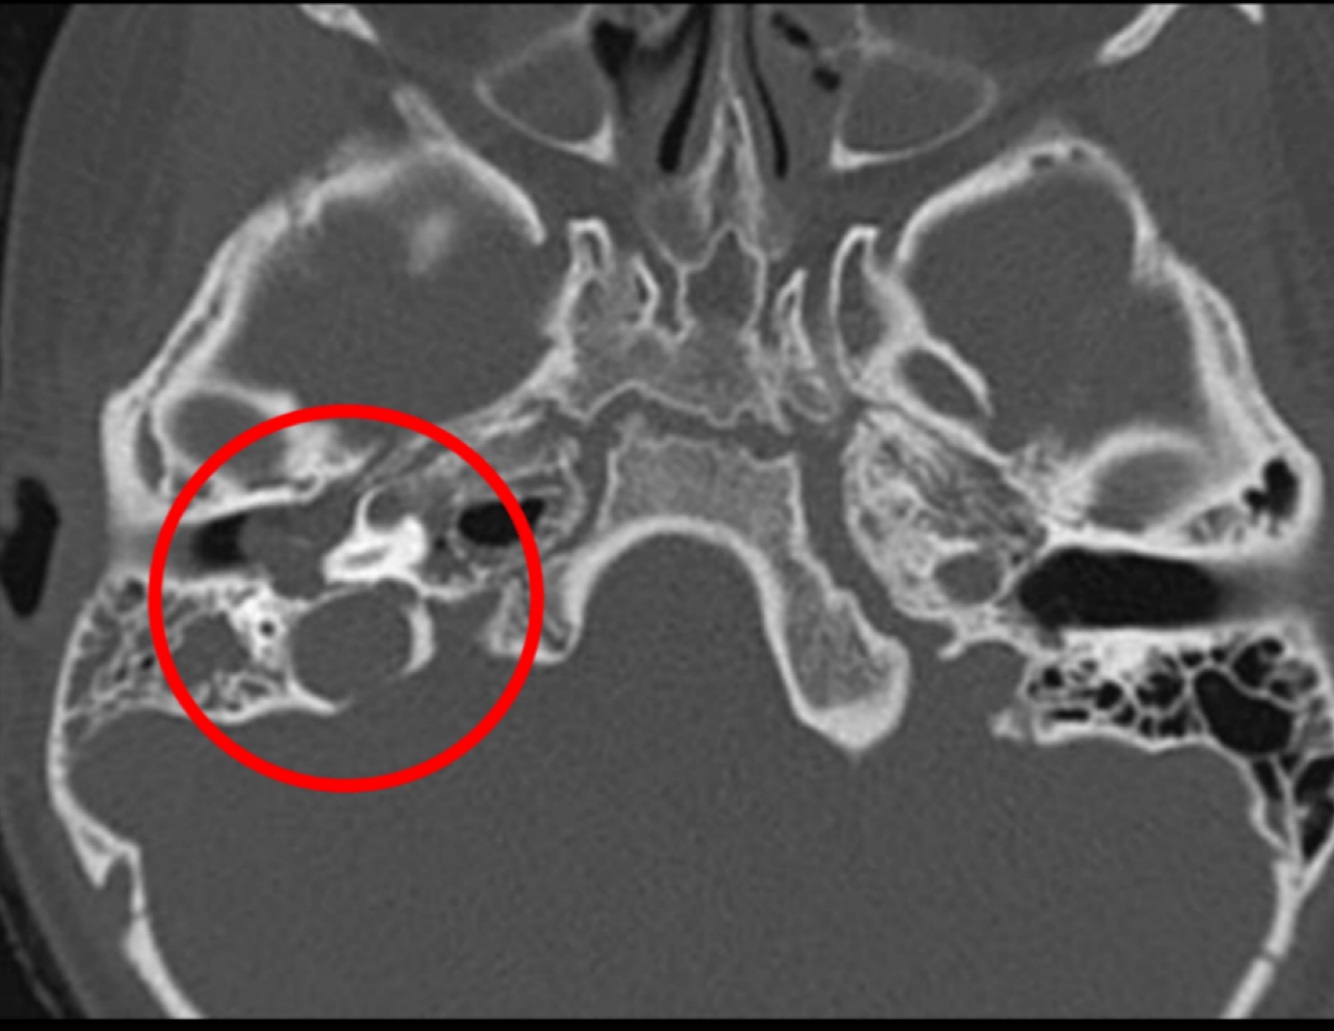

Hallazgos de TC:

• Opacificación de celdillas mastoideas

• Crónico: Esclerodiploico = engrosamiento óseo